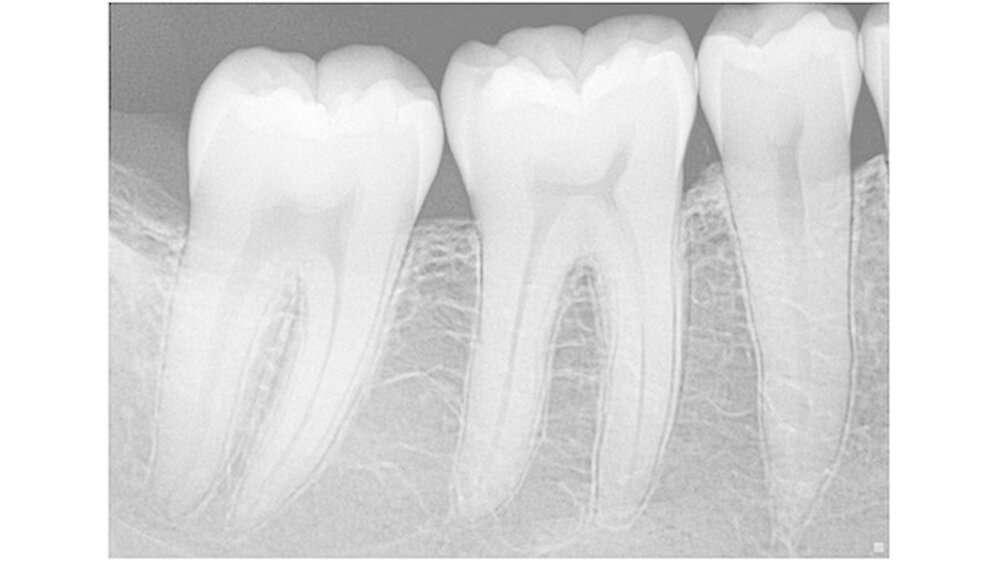

Mit 22 Linienpaaren pro Millimeter beziehungsweise der Darstellung von Details bis auf 12,5 Mikrometer (entsprechend einem ISO-06-Endo-Instrument) werden in der Praxis feinste Strukturen präzise abgebildet. Der Anteil der Speicherfolientechnik lässt sich nur grob schätzen und dürfte zurzeit etwa in Größenordnungen von 60 Prozent gegenüber 40 Prozent (oder 50 zu 50) für Sensoren liegen.

Der Sensor spielt seine Vorteile dort aus, wo es um Schnelligkeit geht, bei der Endo-Kontrollaufnahme oder bei Serienaufnahmen für die Kariesdiagnostik. Auch scheinen in der Sensortechnologie noch Fortschritte möglich, die zu einer Verbesserung der Bildqualität führen könnten. Zum einen lassen sich, parallel zur allgemeinen Entwicklung in der Elektronik, immer mehr Informationen auf einem Chip speichern.

Zum anderen deuten sich auch bei der Umwandlung von Röntgenstrahlen in elektrische Signale Innovationen an: Cäsiumiodid als Scintillator-Material verspricht dank geringer Streuverluste eine bessere Lichtausbeute und damit ein besseres Signal-Rausch-Verhältnis als zuvor übliche Materialien. So kann ein digitaler Sensor heute eine Auflösung von deutlich über theoretisch 30 Linienpaaren pro Millimeter schaffen. In der Handhabung werden sich kabellose Systeme immer stärker durchsetzen, und aktuelle Systeme mit austauschbaren Kabeln reduzieren das Kostenrisiko erheblich.